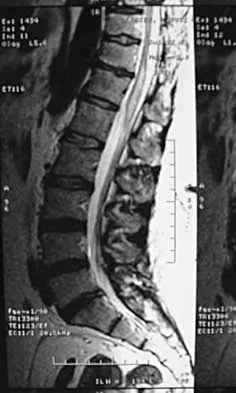

A 16-year-old girl has had pain in the left groin for the past 4 months. She notes that the pain is worse at night; however, she denies any history of trauma and has no constitutional symptoms. There is no history of steroid or alcohol use. Examination reveals pain in the left groin with rotation of the hip. There is no associated soft-tissue mass. A radiograph and MRI scan are shown in Figures 32a and 32b, and biopsy specimens are shown in Figures 32c and 32d. What is the most likely diagnosis?

Explanation

Based on the epiphyseal location and sharp, well-defined borders, the radiograph suggests chondroblastoma. Histologically, multinucleated giant cells are scattered among mononuclear cells. The nuclei are homogenous and contain a characteristic longitudinal groove. Although not seen here, "chicken-wire calcification" with a bland giant cell-rich matrix is also typical for chondroblastoma. Clear cell chondrosarcoma occurs in epiphyseal locations but has a more aggressive histologic pattern and occurs in an older age group. Giant cell tumors occur in the epiphysis but have a more uniform giant cell population histologically. Aneurysmal bone cyst often results in bone remodeling and has a different pathologic appearance. Osteonecrosis has a typical histologic pattern of empty lacunae and necrotic bone. Springfield DS, Capanna R, Gherlinzoni F, et al: Chondroblastoma: A review of seventy cases. J Bone Joint Surg Am 1985;67:748-755. Simon M, Springfield D, et al: Chrondroblastoma: Surgery for Bone and Soft Tissue Tumors. Philadelphia, PA, Lippincott Raven, 1998, p 190.